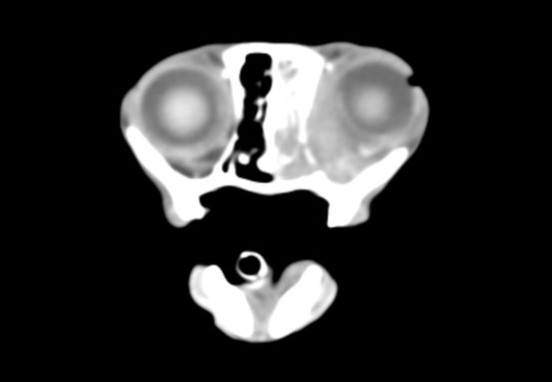

犬の幽門部狭窄

肘頭骨折

脛骨粗面成長板骨折

仙腸関節脱臼